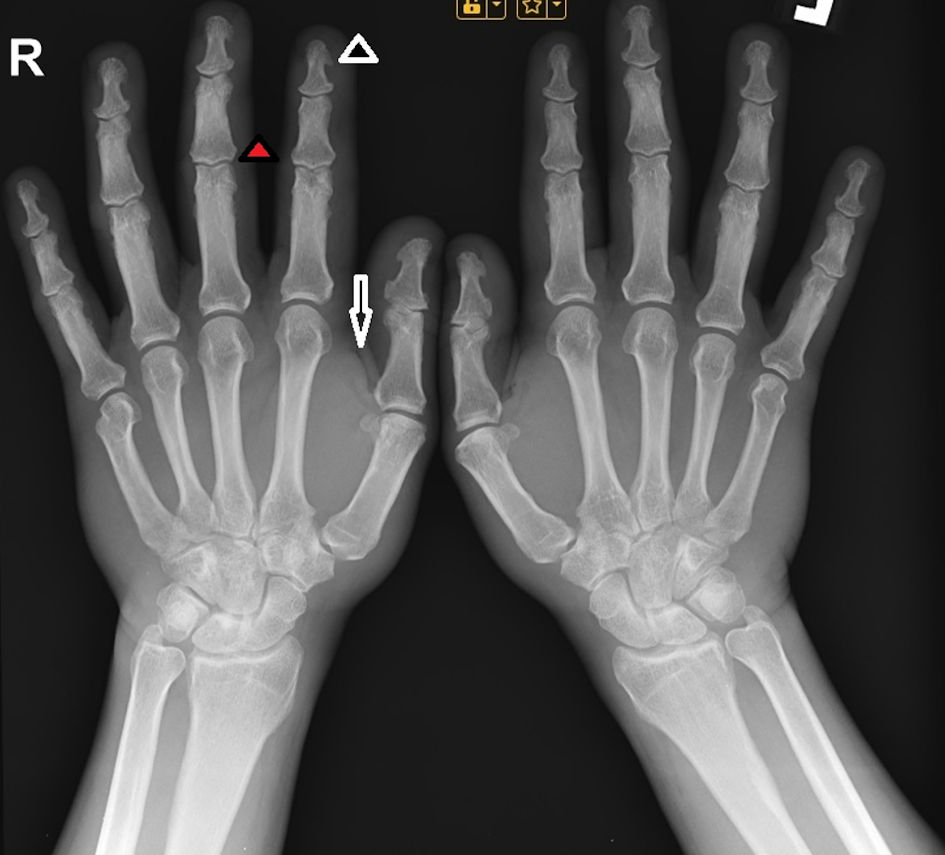

Computerized perimetry was performed, with no evidence of visual field abnormalities. Hand radiography revealed thickened interphalangeal spaces of the distal and middle phalanges of the fingers of both hands and thickened soft tissues (Fig. 3).

Click for large image

Figure 3. X-ray image of the hand, showing hypertrophy of the terminal tufts of the distal phalanges, forming projections similar to spurs (black arrowhead), as well as enlargement of the bases of those phalanges (red arrowhead) and thickened soft tissues (black arrow).